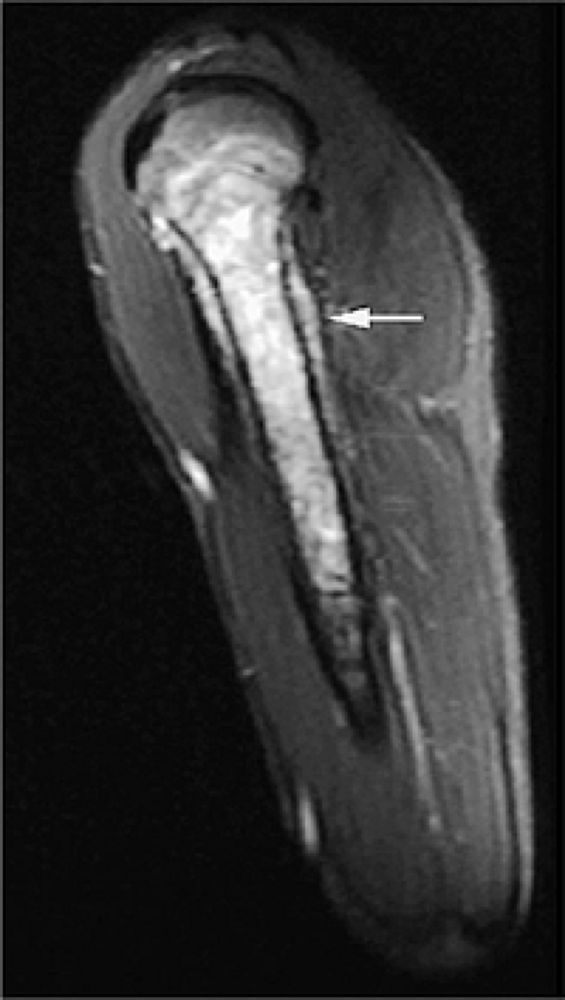

FIGURE 14-4 ● Sagittal fat-suppressed T2-weighted fast spin-echo image demonstrates chondrosarcoma of the humeral shaft. Histologically confirmed hyperintense subcortical tumor infiltration (arrow) is identified.